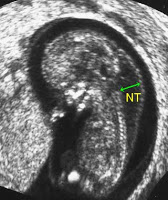

Ense Kalınlığı Ölçümü Ense kalınlığı ölçümü erken gebelikte önemlidir. Gebelikte  11- 14. gebelik haftasındaki taramaya erken gebelik taraması denir. Bu dönemde anne karnındaki bebeklerde kromozomal anormallik ya da sendrom bulunup bulunmadığının tespiti için risk değerlendirmesi yapılır. 11-14. haftalar arasında yapılan ultrason ile ense kalınlığı ölçümü yapılır. Ardından anneden kan alınır, kanda iki adet önemli hormon düzeyine bakılır.  Gebenin yaşı, daha önce anomalili bebek doğurup doğur...

Devamı